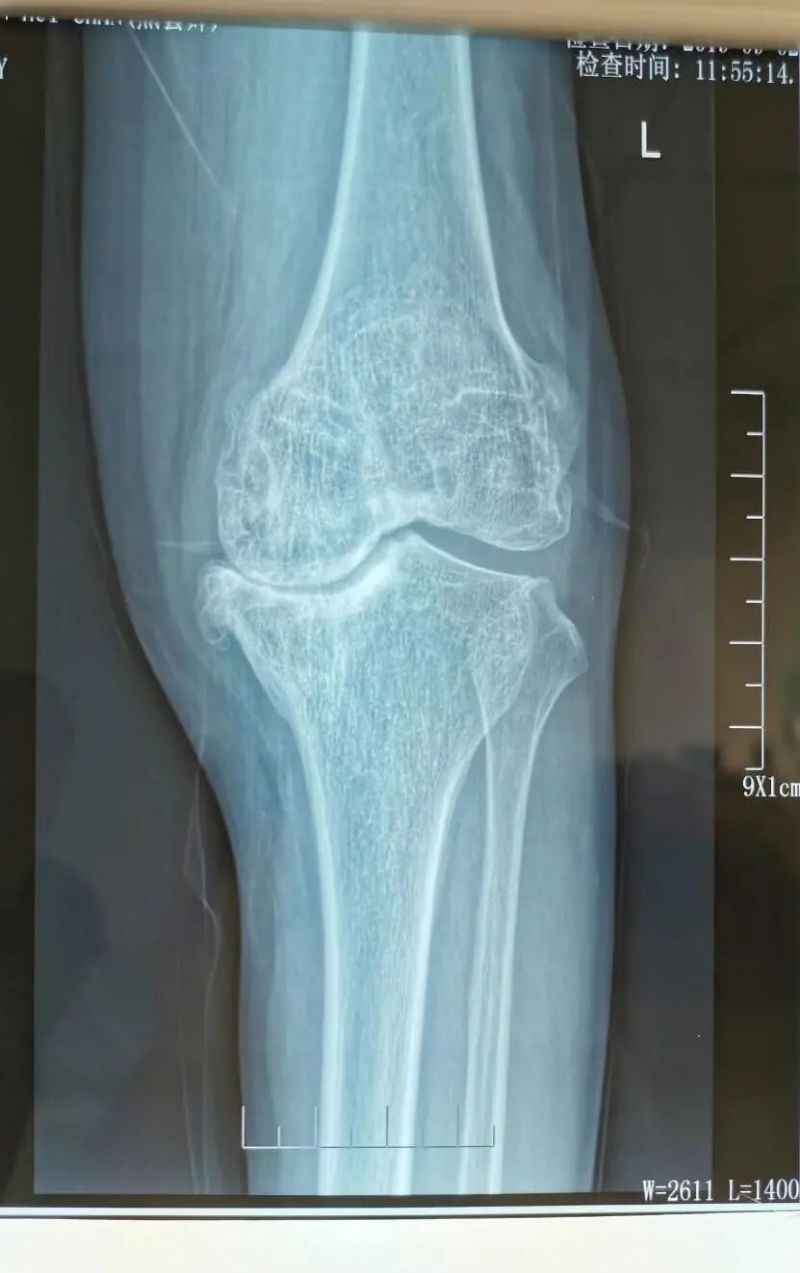

影像學檢查是診斷的重要手段。X線檢查就像給關節拍了一張“照片”,能夠清晰地顯示關節間隙變窄、骨質增生、軟骨下骨硬化等典型表現。而MRI檢查則更像是一部“高清攝像機”,能更清晰地觀察關節軟骨、半月板、滑膜等軟組織的病變情況,為醫生提供更準確的診斷依據。